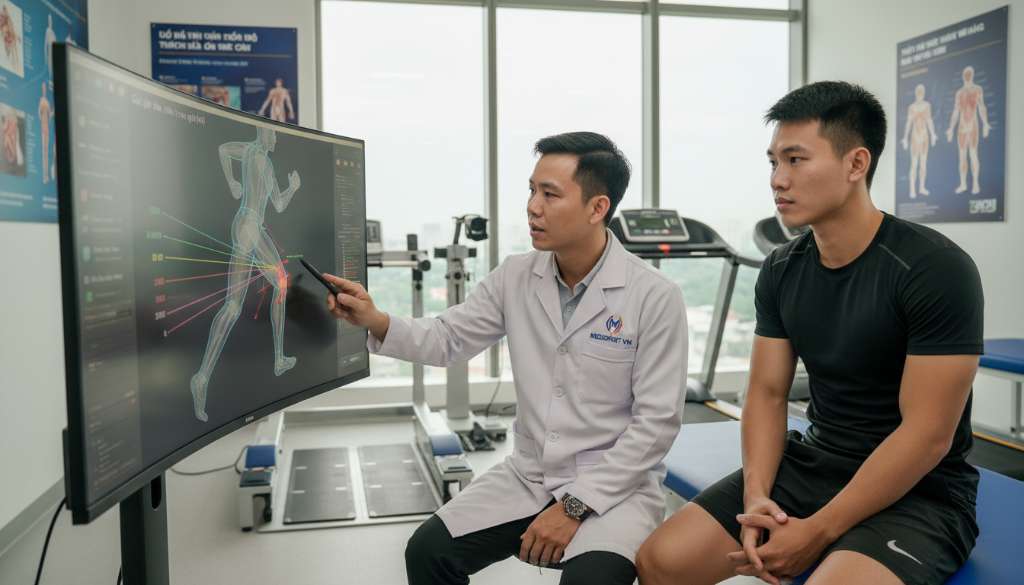

Các dấu hiệu "cảnh báo đỏ" bao gồm: đầu gối bị sưng nóng, có cảm giác bị "kẹt" khớp không thể duỗi thẳng, hoặc cơn đau nhói sắc lẹm khiến bạn phải thay đổi dáng chạy (đi khập khiễng). Trong trường hợp này, việc tìm đến các chuyên gia vật lý trị liệu để thực hiện phân tích dáng chạy (Gait Analysis) chuyên sâu là vô cùng cần thiết. Họ sẽ giúp bạn chỉ ra chính xác điểm yếu cơ học và thiết kế một lộ trình phục hồi cá nhân hóa.